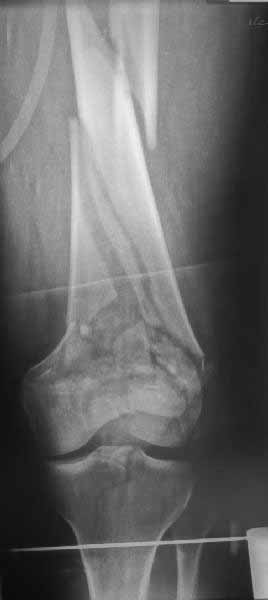

И не обратите, коллега, пока не сделаете четкие анфасные снимки (лучше с дистракцией) где будет четко визуализироваться малоберцовая кость. Думается, что и КТ здесь будет уместно, дабы не пропустить возможное флексионное повреждение (перелом Hoffa).

>Сразу не обратил ваше внимание именно на это, что сломаны оба мыщелка, и больший является именно медиальным мыщелком

Если бы мы имели доступ к тем материалам, которые не были выставлены на сайте, возможно, без подсказки догадались бы, что находится слева или медиально. Неполная информация ведет к неправильной трактовке и к ошибочному выбору фиксаторов. Вместо коллегиальной дискуссии получается беспредметная трата времени. Поэтому высылая материал на любой клинический разбор, желательно подготовиться более профессионально, и предоставить всю информацию про данного больного.

А теперь по поводу лечения перелома. Среди всех чрез/меж-мыщелковых переломов в 38% сопровождются переломом в корональной плоскости, т.е перелом Hoffa. Nork et al, J Orthop Trauma, 87:564, 2005.